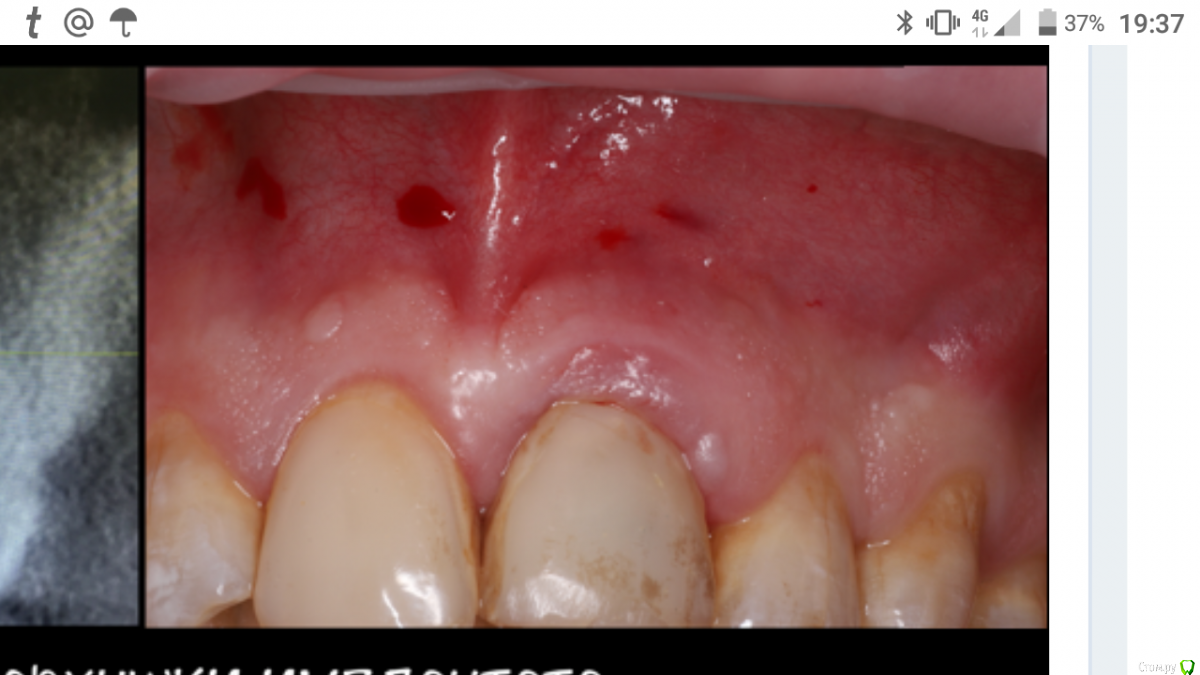

АнтонТЛТ Опубликовано 12 февраля, 2019 Поделиться Опубликовано 12 февраля, 2019 Какие преимущества такого дизайна?Не будет как тут. Было/стало.Внимание на мукогингивальную границу. 1 Ссылка на комментарий

Евгений Ходыкин Опубликовано 12 февраля, 2019 Поделиться Опубликовано 12 февраля, 2019 Не будет как тут. Было/стало.Внимание на мукогингивальную границу.Речь про горизонтальный рубец?? Ссылка на комментарий

АнтонТЛТ Опубликовано 12 февраля, 2019 Поделиться Опубликовано 12 февраля, 2019 Речь про горизонтальный рубец??Ага Ссылка на комментарий

Евгений Ходыкин Опубликовано 12 февраля, 2019 Поделиться Опубликовано 12 февраля, 2019 АгаДак тут тупо по мукогингивальной границе разрез. Ясен перец в рубцах усё будет Ссылка на комментарий

AlexanderGudkov Опубликовано 12 февраля, 2019 Автор Поделиться Опубликовано 12 февраля, 2019 Дак тут тупо по мукогингивальной границе разрез. Ясен перец в рубцах усё будет Да неее, оступил))) Ссылка на комментарий

АнтонТЛТ Опубликовано 12 февраля, 2019 Поделиться Опубликовано 12 февраля, 2019 Да неее, оступил)))Отступай на половину высоты десны) Ссылка на комментарий